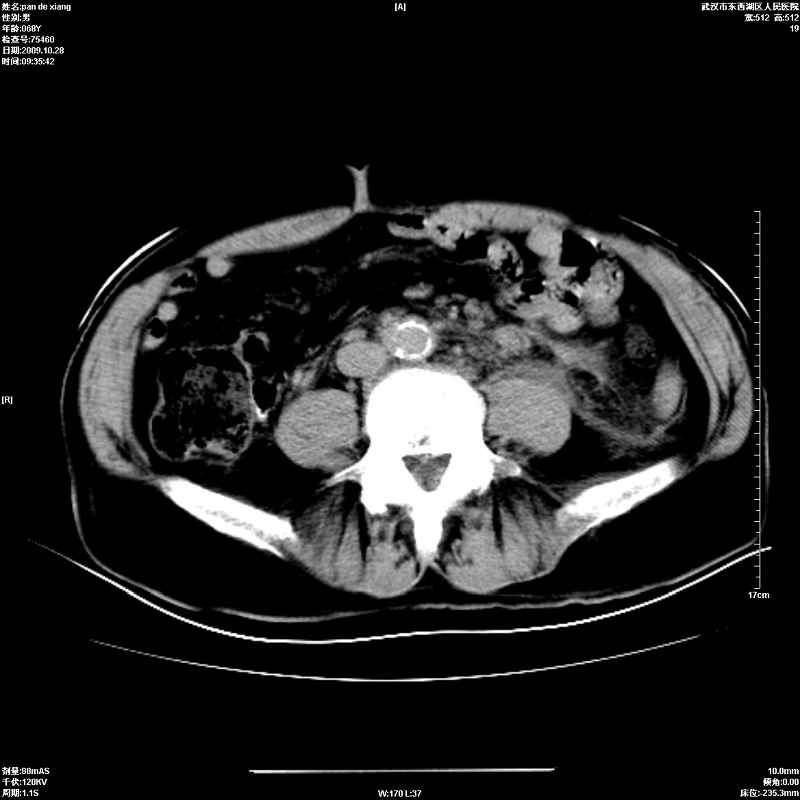

以下是引用杀毒软件在2009-10-28 20:41:00的发言:[br]结合临床考虑---白血病双肾改变或淋巴瘤。

以下是引用zxl51642在2009-10-29 9:59:00的发言:[br]结合临床“单克隆免疫球蛋白血症”,考虑双肾为继发损害并肾功能不全(尿中大量igg及少量iga、igm等大分子免疫球蛋白滤出所致继发损害),椎前软组织肿块为髓外造血。与浆细胞瘤有区别,平扫时有战友说的很清楚。